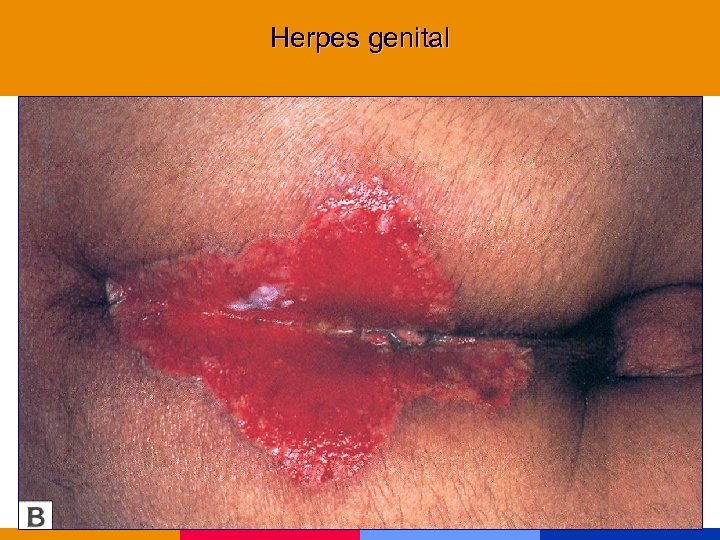

Herpes mucocutáneo crónico

Herpes mucocutáneo crónico

Herpes genital

Herpes genital